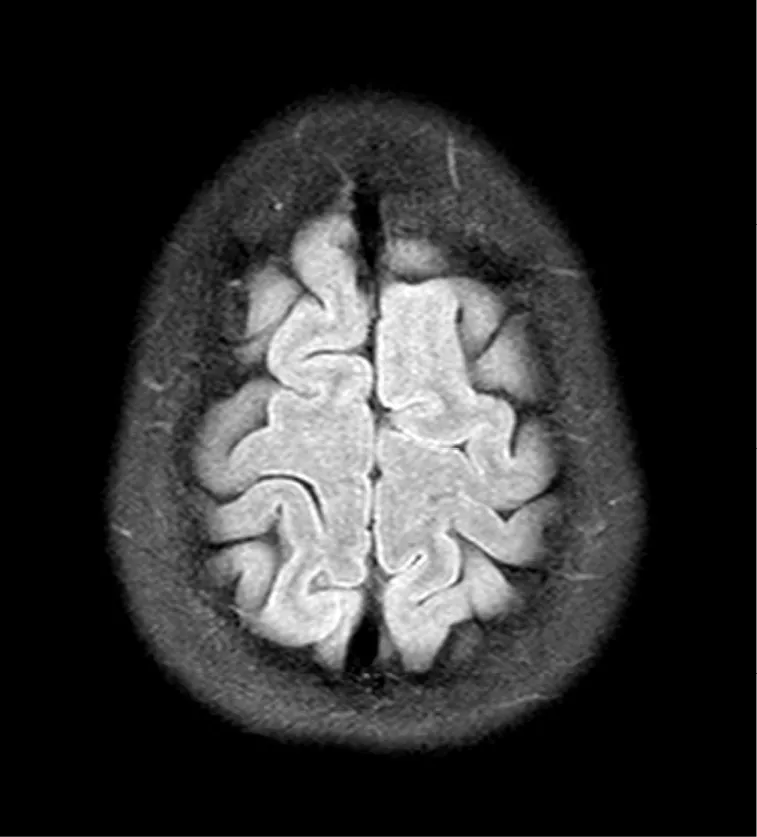

Medical imaging technologies can help diagnose and monitor patients' diseases, but they do not capture the lived experience of illness. In this volume, Devan Stahl shares her story of being diagnosed with multiple sclerosis with the aid of magnetic resonance images (MRIs). Although clinically useful, Stahl did not want these images to be the primary way she or anyone else understood her disease or what it is like to live with MS. With the help of her printmaker sister, Darian Goldin Stahl, they were able to reframe these images into works of art. The result is an altogether different image of the ill body. Now, the Stahls open up their project to four additional scholars to help shed light on the meaning of illness and the impact medical imaging can have on our cultural imagination. Using their insights from the medical humanities, literature, visual culture, philosophy, and theology, the scholars in this volume advance the discourse of the ill body, adding interpretations and insights from their disciplinary fields.

Three months later I was given my first MRI scan and referred to a neurologist. It took the neurologist all of thirty seconds to diagnose me after examining my scans.

How could he tell? What is he seeing? What is going to happen to me? Didnât I see this coming? Didnât I do an Internet search on this? Didnât the other doctors tell me I was going to be all right? Were they lying? Did they know? Did they suspect? How can he know I have a devastating illness just looking at those gray blobs? What is MS? Itâs bad . . . itâs neurological . . . itâs debilitating . . . wait, I know someone with MS . . . a woman who goes to my church has MS. Every Sunday she comes and goes in a van because she is a quadriplegic.

âHow can you be sure?â I managed. He looked confused. âIâm not sure what you are seeing in those pictures,â I followed up.

âIâm a specialistâ he assured me, in his most proud and patronizing tone. âI know what I am looking for.â

My body shrinks in and I stare at the floor, then back at the computer, then back at the floor. All the energy leaves my body. I have no more questions. I am empty. I curl up in the fetal position and a large needle is inserted into my spine; my diagnosis is confirmed. I have multiple sclerosis.